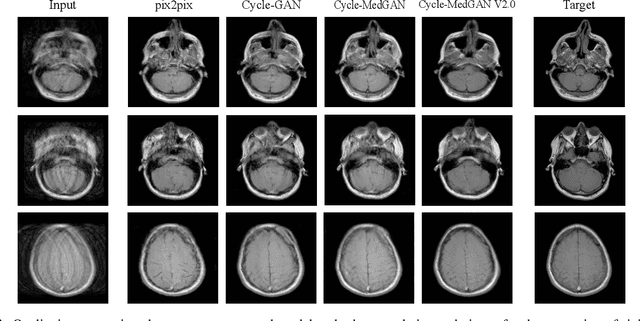

Abstract:Motion is one of the main sources for artifacts in magnetic resonance (MR) images. It can have significant consequences on the diagnostic quality of the resultant scans. Previously, supervised adversarial approaches have been suggested for the correction of MR motion artifacts. However, these approaches suffer from the limitation of required paired co-registered datasets for training which are often hard or impossible to acquire. Building upon our previous work, we introduce a new adversarial framework with a new generator architecture and loss function for the unsupervised correction of severe rigid motion artifacts in the brain region. Quantitative and qualitative comparisons with other supervised and unsupervised translation approaches showcase the enhanced performance of the introduced framework.